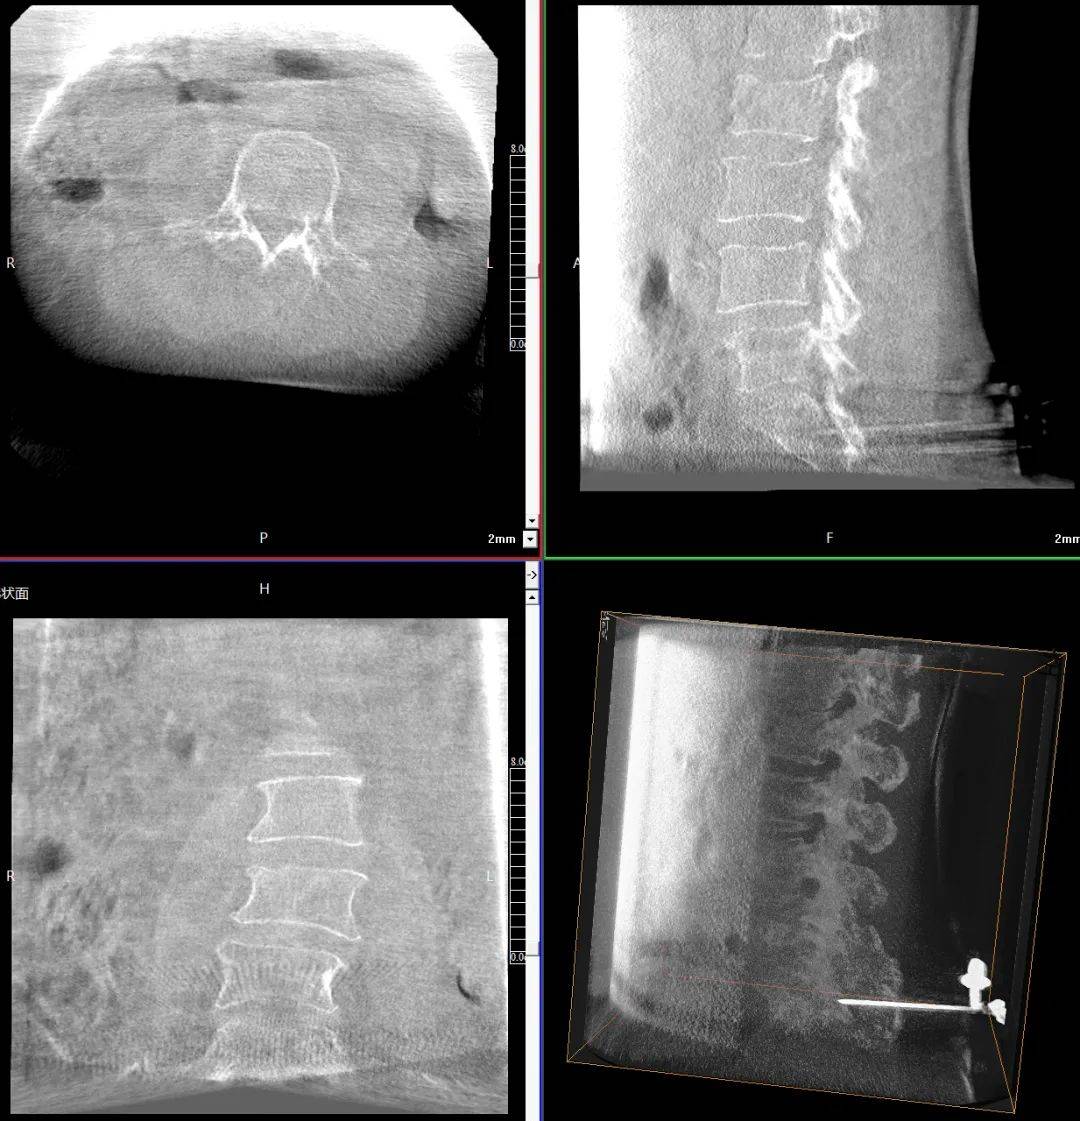

臨床表現(xiàn):患者主訴腰背部劇烈疼痛,活動受限;查體證實(shí)腰背部局部壓痛、叩擊痛明顯,尤其在受累椎體區(qū)域;影像學(xué)檢查顯示多節(jié)段椎體壓縮性骨折,椎體高度明顯降低,椎體形態(tài)不規(guī)則,椎體扭曲畸形,椎弓根狹窄。

患者術(shù)前影像

手術(shù)指征:疼痛難以耐受,保守治療(如臥床休息、止痛藥物等)效果不佳;多節(jié)段椎體壓縮性骨折,椎體高度明顯降低,脊柱穩(wěn)定性受損。